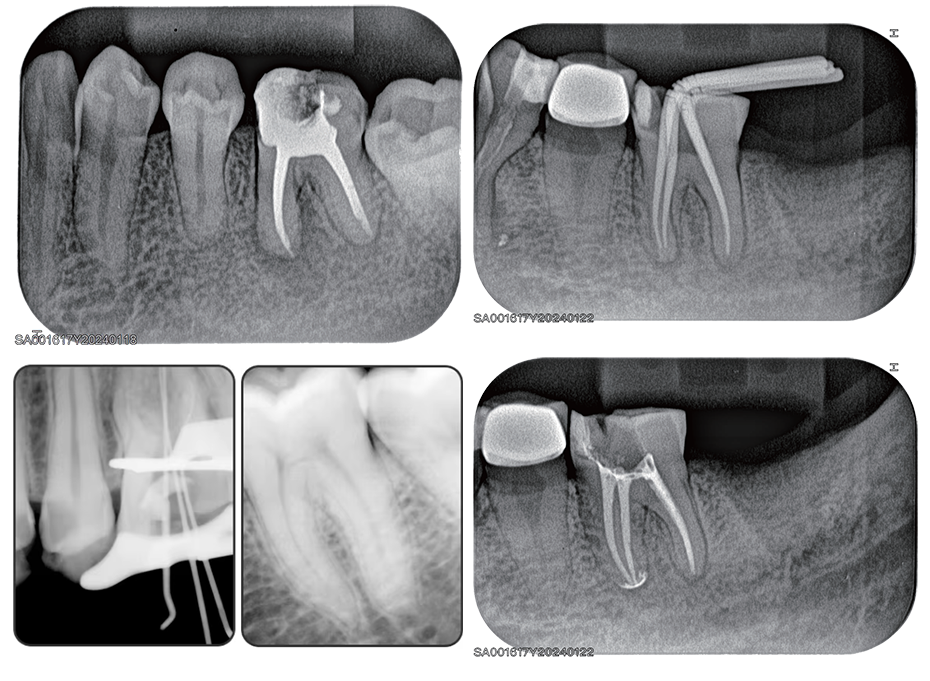

Røntgen billedkvalitet

Diagnostisk billedkvalitet

Med høj opløsning, fine gråtoner og stabil scanning leverer PicoScan billeder, der understøtter præcis diagnose og sikker klinisk vurdering.